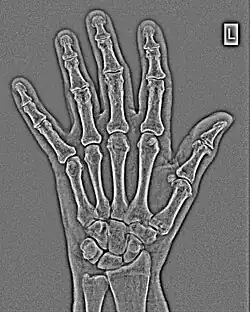

FFTs can also be calculated in two-dimensions to give results such as those in Figure 1.27. Since Fourier analysis generates results in terms of both positive and negative spatial frequencies, these can be plotted in the form of a 2D image so that the maximum frequency lies at the origin and those for the horizontal and vertical directions are shown increasing towards that origin. The modulation at different spatial frequencies is represented using a grey-scale. Low frequency bands can be seen along the horizontal axis in the figure, for example, representing the horizontal periodicity of image data from the fingers, while finer bands along the y-dimension are indicative of a periodicity of image data from the various metacarpophalangeal joints. Higher frequency features can also be seen running diagonally in this 2D-FFT, representative of the trabecular structure of the bones, for example.

The essence of this approach is that it can be used to produce a range of image processing effects by enhancing and/or suppressing features in the 2D-FFT and then converting the result back into the spatial domain using the IFT, as illustrated in Figure 1.28. Such image manipulations are considered in more detail in a later chapter. Note that the form of image processing demonstrated in the figure is for purely illustrative purposes and bears no direct medical significance.